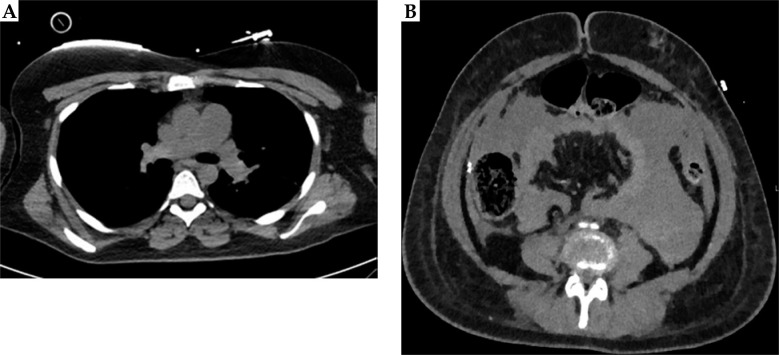

Case presentation: This case series reported three women, who experienced near-fatal saddle pulmonary embolisms shortly after undergoing high-dose-rate brachytherapy for locally advanced cervical cancer. In one patient, pulmonary saddle embolism led to hypovolemic shock due to intra-abdominal hemorrhage post-resuscitation, necessitating emergency decompressive laparotomy. Another case was complicated by neurological symptoms consistent with a stuttering stroke, following mechanical pulmonary thrombectomy.